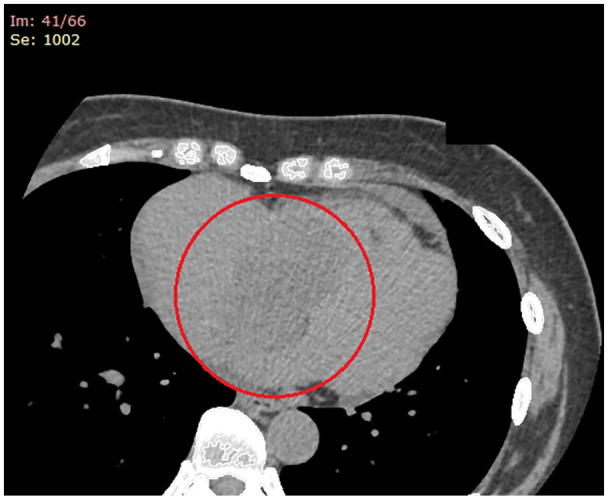

右心房黏液瘤是一种非常罕见的心脏肿瘤,可引起毁灭性的并发症。这些肿瘤能够通过静脉回流和三尖瓣流入阻塞而产生右侧心力衰竭。在此,我们描述了一位52岁的女性,表现为典型的rHF症状,为巨大RAM的临床后遗症。临床医生应认识到RAMs是rHF的非典型病因,在诊断检查和早期手术切除中补充成像方式是关键的管理策略。

Right atrial myxomas (RAMs) are exceedingly rare cardiac tumors that can incur devastating complications. These tumors are capable of producing right-sided heart failure (rHF) through obstruction of venous return and tricuspid inflow. Herein, we describe a 52-year-old woman presenting with classic symptomatology of rHF as clinical sequelae of a giant RAM. The clinician should be cognizant of RAMs as an atypical etiology of rHF, and the complementary imaging modalities in the diagnostic work-up and early surgical resection as key management strategies.